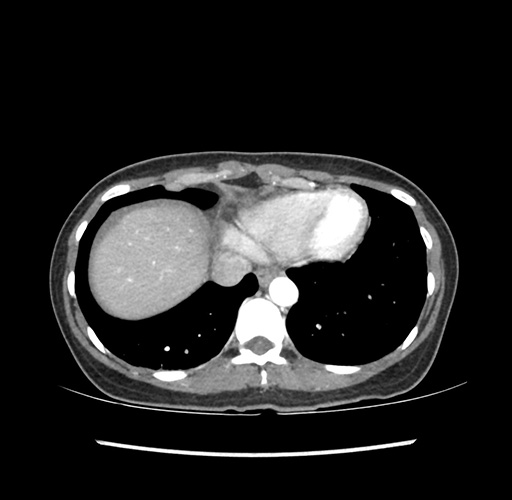

Imaging Analysis

Look through the patient's CT scan to identify any areas of concern for the necessary procedure.

Based on your CT findings, which issue(s) would give reason for "planned slowing down moment(s)" in this case?